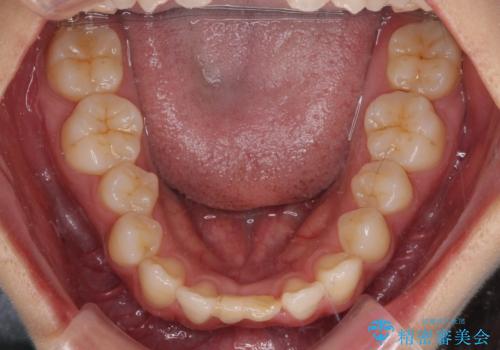

- 下顎前歯に乳歯が残っており、欠損もしていることを気にして来院された患者様です。

ワイヤー装置により矯正治療を行うとともに舌突出癖改善のためのトレーニングをしっかりと行っていただき、咬み合わせが安定した位置となったタイミングで下顎前歯にブリッジの仮歯を装着していく計画としました。

矯正治療終了後に速やかにオールセラミックブリッジを装着していくこととしました。

結婚式の予定があるとのことで、できる限り歯列を整え、挙式直前で残った乳歯を抜歯してブリッジの仮歯を装着するプランを立てたのですが、途中妊娠をされたため、麻酔をするタイミングを検討し、うまく前歯を整えることができました。